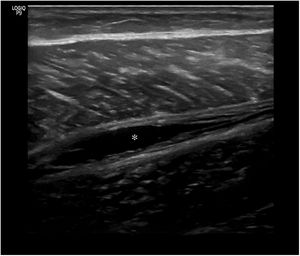

El músculo sano, ecográficamente, presenta una ecogenicidad inferior a la del tejido celular subcutáneo y una disposición de finas líneas paralelas ecogénicas, múltiples, en cortes longitudinales, en «pluma de ave» (fig. 1), y aspecto reticular en corte transversal «aspecto moteado» (fig. 2), rodeados por la fascia hiperecogénica y en su interior la unión miotendinosa también hiperecogénica4. En ecografía se describen 4 grados de lesión muscular propuestos por Peetrons en 20027 (tabla 2).

En la ecografía en el 50% de las lesiones grado 1 (fig. 3) se observará hiperecogenicidad en la lesión. En las de grado 2 (fig. 4) y 3 (fig. 5) se visualizarán regiones hipoecoicas indicativas de líquido adyacente a las fibras musculares. Se considera curación normal cuando hay una reducción en el tamaño o resolución de la región hiperecogénica, del hematoma o de la colección líquida. Si se demuestra tejido cicatricial durante el seguimiento es de importancia ya que, a mayor cicatrización, mayor riesgo de daño recurrente3.